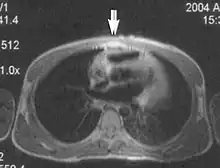

Metal artifacts occur at interfaces of tissues with different magnetic susceptibilities, which cause local magnetic fields to distort the external magnetic field. This distortion changes the precession frequency in the tissue leading to spatial mismapping of information. The degree of distortion depends on the type of metal (stainless steel having a greater distorting effect than titanium alloy), the type of interface (most striking effect at soft tissue-metal interfaces), pulse sequence and imaging parameters. Metal artifacts are caused by external ferromagnetics such as cobalt containing make-up, internal ferromagnetics such as surgical clips, spinal hardware and other orthopaedic devices, and in some cases, metallic objects swallowed by people with pica.[3] Manifestation of these artifacts is variable, including total signal loss, peripheral high signal and image distortion (Figs 3 and 4).[1] Reduction of these artifacts can be attempted by orientating the long axis of an implant or device parallel to the long axis of the external magnetic field, possible with mobile extremity imaging and an open magnet. Further methods used are choosing the appropriate frequency encoding direction, since metal artifacts are most pronounced in this direction, using smaller voxel sizes, fast imaging sequences, increased readout bandwidth and avoiding gradient-echo imaging when metal is present. A technique called MARS (metal artifact reduction sequence) applies an additional gradient, along the slice select gradient at the time the frequency encoding gradient is applied.